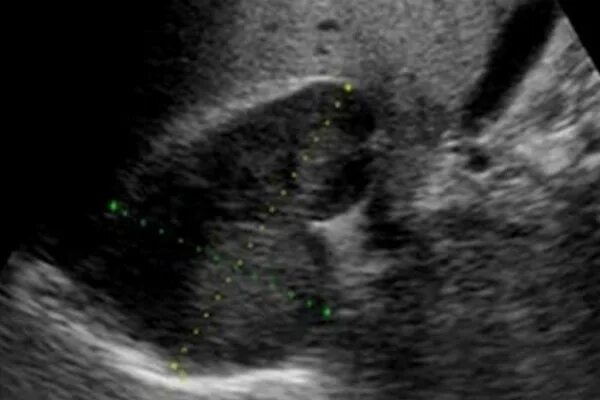

Узи надпочечников и забрюшинного пространства подготовка